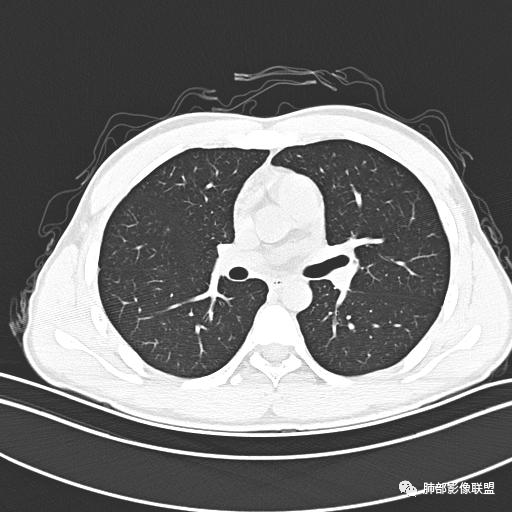

小强:青年,发热,皮疹;双肺散在结节,周围磨玻璃,点晕征,疱疹病毒感染,鉴别荚膜组织胞浆菌,结核。 大雄:青年,急性起病,发热伴全身皮疹2天,抗病毒治疗体温有下降。双肺随机分布大小不等类圆结节,“点晕征”。考虑水痘-疱疹病毒(VZV)血播询问接触史,查体皮疹分布以及形态基本可诊断。 王开金江津中心医院呼吸科:青年男性,起病急,病程短,以发热,皮疹为首发症状,感染指标以单核细胞升高为主,胸部ct双肺多发结界,周围有晕,点晕表现,随机分布,同意於老师意见,水痘疱疹病毒血流感染累及肺。 王秀仙:双肺多发大小不等结节,周围有晕,边缘模糊,呈点晕征表现。青年,急性起病,发热伴全身皮疹2天,抗病毒治疗体温有下降。考虑疱疹病毒。鉴别荚膜组织胞浆菌。 傅昌瑜:19岁男性,发热、全身皮疹2天,单核细胞增高,双肺多发结节,结节边缘见边界不清磨玻璃影。点晕征+发热、全身皮疹+单核细胞增高——考虑水痘-带状疱疹病毒肺炎。 一切∮随缘:年轻男性,发热,皮疹两天,实验室,CRP,PCT增高,影像:双肺多发散在磨玻璃结节,边界欠清,大小不等,呈点晕征改变,以血管束周围分布为主,局部血管束略增粗,其它无明显改变,考虑:1:病毒性肺炎(水痘疱疹病毒?不知道皮肤有无改变)2:真菌(组织胞浆菌,血管侵袭性肺曲霉)3:GPA4:寄生虫(实验室没有看到嗜酸细胞增高) 赵山河:双肺散在结节,周围有晕,边缘模糊,呈点晕征表现。青年,急性起病,发热伴全身皮疹2天,抗病毒治疗体温有下降。考虑水痘—疱疹病毒感染。洪桥爱:青年男性,发热、皮疹2天,伴瘙痒,皮疹于面部首发,之后进展至全身,虽然没有对皮疹进行描述,但是从出疹时间及皮疹进展情况,伴瘙痒,应该就是个水痘患者;CT提示双肺随机分布结节影,部分结节伴有边界不清晕征,考虑水痘血播肺。 刘强:年轻男性,急性起病,皮疹,发热,抗感染治疗体温下降,说明有效。影像表现为散在点晕征,感染类疾病谱(疱疹病毒,真菌,结核),结合年龄,皮肤皮疹,考虑水痘-疱疹病毒性肺炎。 小兜:男性,19岁,发热皮疹两天,颜面部至全身,CRP,降钙素及单核增高。CT示双肺散在小结节,周围伴磨玻璃影,点晕征,考虑为水痘-带状疱疹病毒(varicella-zoster virus,VZV)肺炎 必有路:青年,皮疹+发热+“点晕征”→水痘-疱疹病毒(VZV) 许慧良:青年男性患者,发热、皮疹2天,体温最高38.5℃,第3天皮疹扩展至全身,伴瘙痒,胸部CT:双肺多发随机分布的小结节,结节周边见边界模糊的晕征,考虑水痘病毒感染流心明智:男,19,急性起病,发热伴全身皮疹2天。出疹顺序头→全身,抗病毒有效。胸部CT:两肺多发大小不等类圆形实性小结节影,随机分布,结节周围环绕GGO,边界模糊,呈点晕征。出疹特点是关键,未提示。考虑:血播病毒性肺炎,水痘-疱疹病毒?麻疹?鉴别荚膜组织胞浆菌、TB、血管炎、寄生虫等。 浪迹天涯:病灶多为5-10mm大小结节,结节周围可见磨玻璃样的晕环,常多发,可分布于肺内任何区域,考虑水痘—带状疱疹病肺炎如果短时间内有新的一个区域浸润,更加能说明,